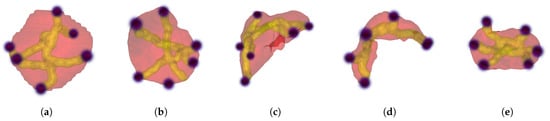

- Extreme point selection

- Initial segmentation from scribbles via random walker (RW) algorithm

- Segmentation via deep fully convolutional network (FCN), where we explore several variations on the training scheme

- (a)

- Without RW and Dice loss

- (b)

- With RW but without the extra point channel and Dice loss

- (c)

- With RW and Dice loss

- (d)

- With RW and Dice loss and point loss

- (e)

- With RW and Dice loss and point loss and attention

- (f)

- With RW and Dice loss and point loss and point attention

- Regularization using random walker algorithm

2.1. Step 1: Extreme Point Selection

2.2. Step 2: Initial Segmentation from Scribbles via Random Walker Algorithm